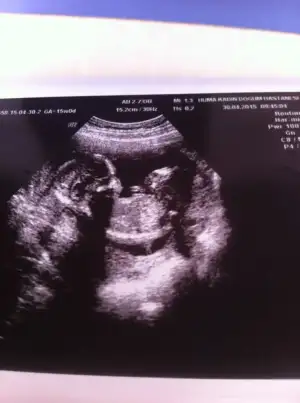

Cinsiyetimiz erkek

Eklentiler

• IMG_1320.webp

IMG_1320.webp

24,6 KB · Görüntüleme: 174

• IMG_1321.webp

IMG_1321.webp

31,6 KB · Görüntüleme: 177

• IMG_1322.webp

IMG_1322.webp

25,8 KB · Görüntüleme: 186